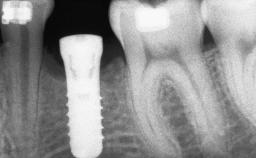

Bone Augmentation Horizontal|Staged

Augmentation Materials Autogenous chips|Autogenous block(s)|Membrane

Bone Volume Deficient horizontally, requiring prior grafting